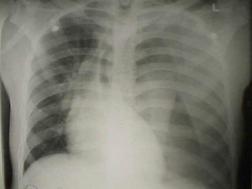

Pneumotorace sufocant bilateral Pneumotorace sufocant stang

Pneumotorace

sufocant stang Pneumotorace

sufocant drept Pneumotorace

sufocant drept

Pneumotorace deschis Pneumotorace

deschis Traumatism

Traumatism toracic deschis Hemotorace stang masiv

Hemotorace stang masiv Hemotorace stang masiv

Hemotorace

drept masiv Hemotorace stang

Imagine CT Radiografie efectuata in ortostatism